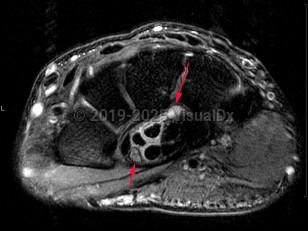

Mild carpal tunnel syndrome is typically not associated with dermatologic findings. When long-standing, autonomic nerve dysfunction occurs, resulting in necrotic carpal tunnel syndrome. Dermatologic manifestations will then include bullae, ulcers, hypohidrosis, vasospasm, and Raynaud phenomenon. Nail changes may also occur and may be a clue to diagnosis of carpal tunnel syndrome.

There are case reports of carpal tunnel-associated nail changes in children and young adults; however, it is very rare in children. For late stage carpal tunnel syndrome presenting in children, genetic or metabolic causes should be explored, although there are reports of sporadic cases. These include lysosomal storage diseases (familial thickening of the transverse ligament and diabetes mellitus). Other reported causes are repetitive wrist motion, median nerve fibrolipomas or hemangiomas, hemophilia, automutilation, and trauma.